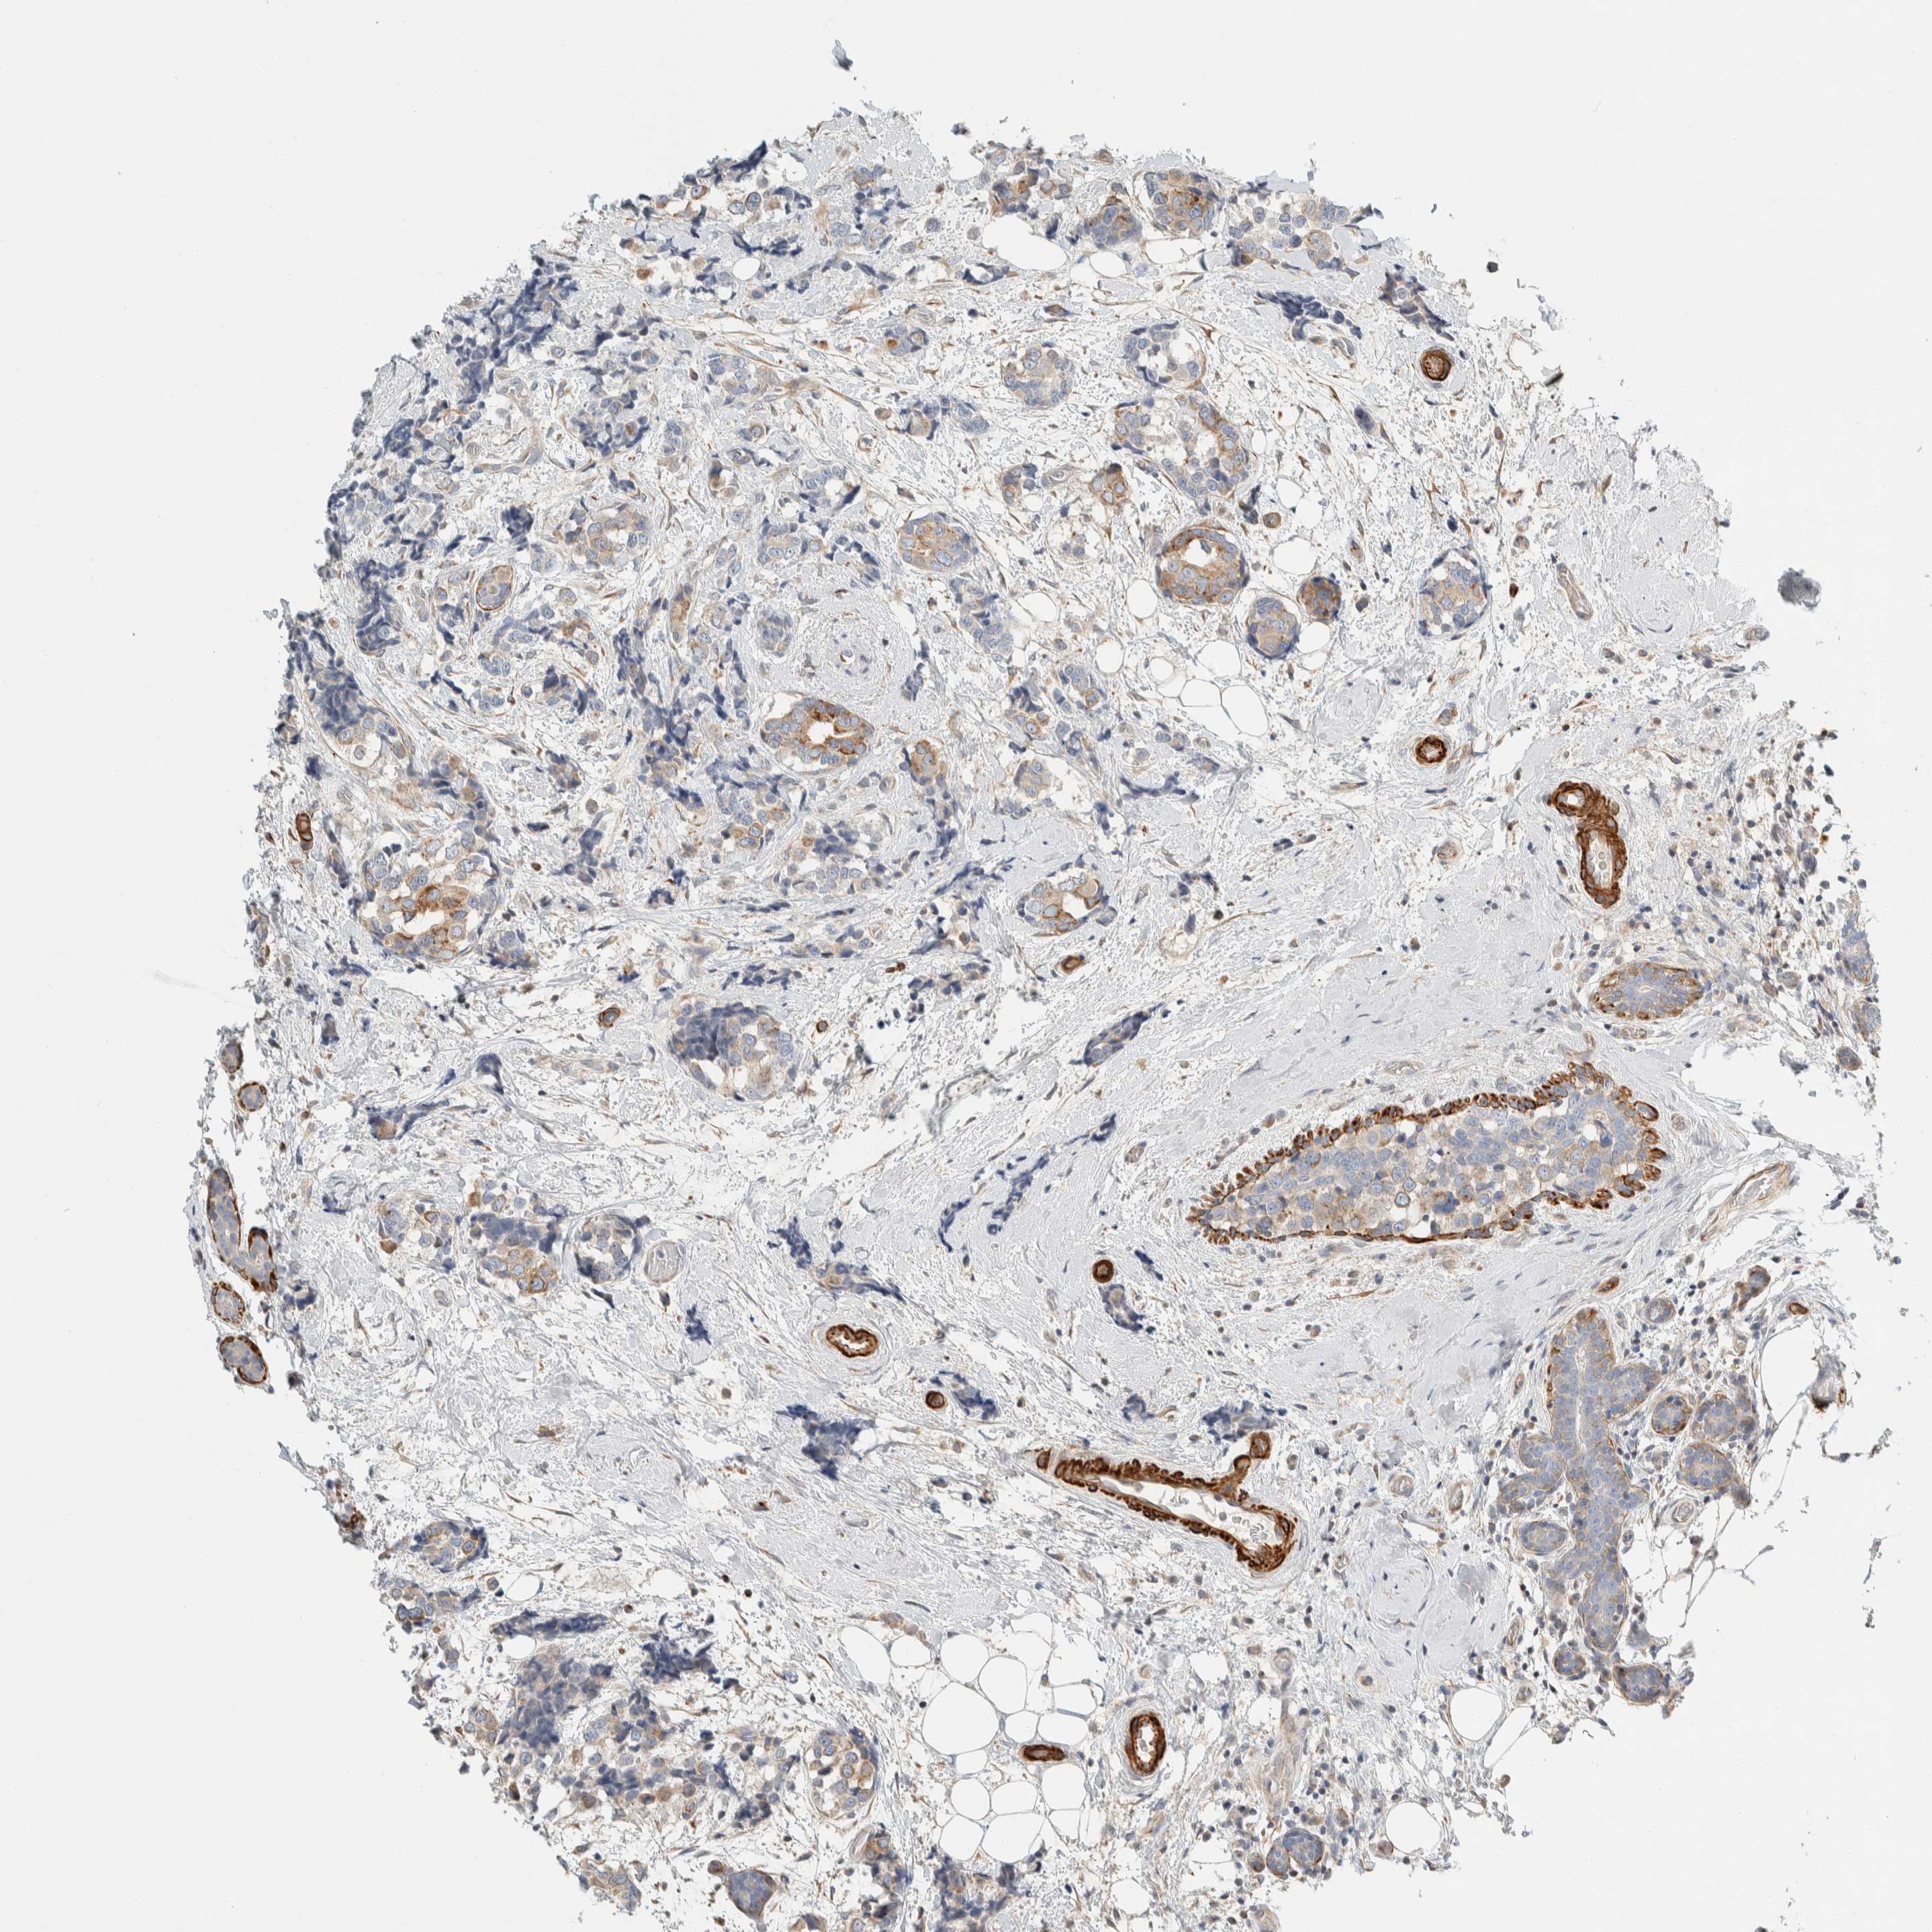

CANCER BREAST CANCER Show tissue menu

BRCA TCGA BRCA VALIDATION PROTEIN EXPRESSION